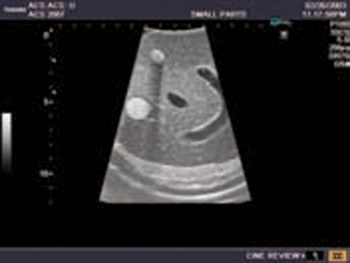

Ultraschall-Modell für die intraoperative abdominelle und laparoskopische Sonografie Eigenschaften

- Ein künstliches Modell für die Ausbildung eines Anfängers nach Demonstration durch einen Fachmann.

- Die genaue Darstellung der Anatomie der Leber und Gallenwege, des Pankreas und des übrigen Abdomens entspricht den höchsten Anforderungen an eine exzellente Ausbildung: offene intraoperative Sonografie von Leber, Gallengängen und Pankreas; die laparoskopische Untersuchung des Gallensystems zur Prüfung auf eine Steinbildung und Beurteilung auf Leber- und Pankreasläsionen etc.

- Die weichen Materialien des Modells ermöglichen eine realistische Sondenführung. Verschiedene Läsionssimulationen wie Gallensteine und -zysten, solide Tumore (echoarm, echoreich, entsprechend der Echostruktur des simulierten Objekts) in Leber, Pankreas und Nieren.

Die pathologischen Befunde umfassen:

Läsionen der Leber (solide und zystische), Gallenblasen- und Gallengangssteine, Pankreastumore (einer dringt in die Portalvene ein), Läsionen der Milz und beider Nieren, Nebennierentumor links.